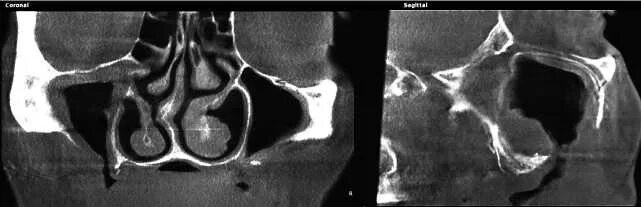

Как лечить утолщение слизистой верхнечелюстной пазухи